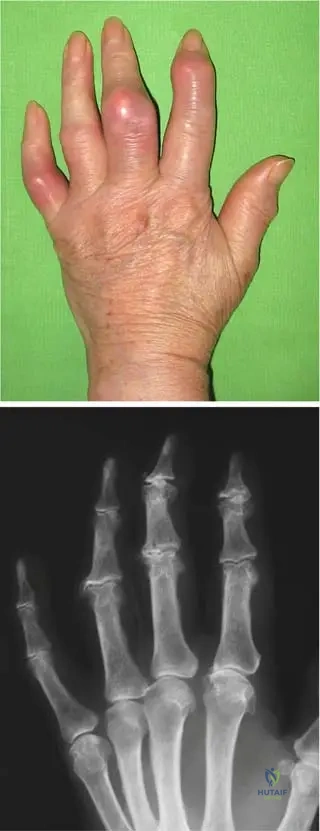

A 70-year-old male presents with chronic, progressively worsening hand deformities. On examination, his fingers are deformed, and the phalangeal joints are swollen with tight, hot, and dark-red skin. He also reports occasional low-grade fever.

Rationale: The clinical context for Fig. 7.2 a, b directly describes this scenario as "Exacerbation of a chronic gout process in the hand: the fingers are deformed, the joints of the phalanges are swollen, with tight, hot, and dark-red skin, frequently accompanied by some general symptoms (fever, higher sedimentation rate, increased number of white blood cells)." While acute symptoms are present, the underlying chronicity and deformities point to an exacerbation of a chronic condition.

A 68-year-old male with a long history of gout presents with chronic hand pain and deformities. A radiograph of his hand is obtained.

Rationale: The clinical context for Fig. 7.2 b states that the radiograph of a patient with chronic gout presents "narrowed joint spaces, and typical punched-out periarticular lytic lesions." These are classic radiographic findings for chronic gouty arthropathy. Option B describes some features that can be seen, but "punched-out lytic lesions" are highly characteristic.

A 75-year-old male with poorly controlled gout for several decades presents with multiple firm, non-tender nodules in his palmar region.

Rationale: The clinical context for Fig. 7.3 a, b explicitly states, "Late stage of gout: numerous subcutaneous tophi are present in the palmar region." Tophi are characteristic subcutaneous deposits of urate crystals in chronic, uncontrolled gout. Heberden's and Bouchard's nodes are associated with osteoarthritis, and rheumatoid nodules with rheumatoid arthritis.

A 72-year-old male with a history of chronic gout presents with hand pain. Radiographs reveal soft tissue masses around the small joints of the hand.

Rationale: The clinical context for Fig. 7.3 b states, "These tophaceus gouty deposits are also visible in the radiograph around the small joints of the hand." Tophi are the hallmark of late-stage chronic gout and can appear as soft tissue masses on radiographs. Chondrocalcinosis is calcification of cartilage, typically associated with pseudogout.